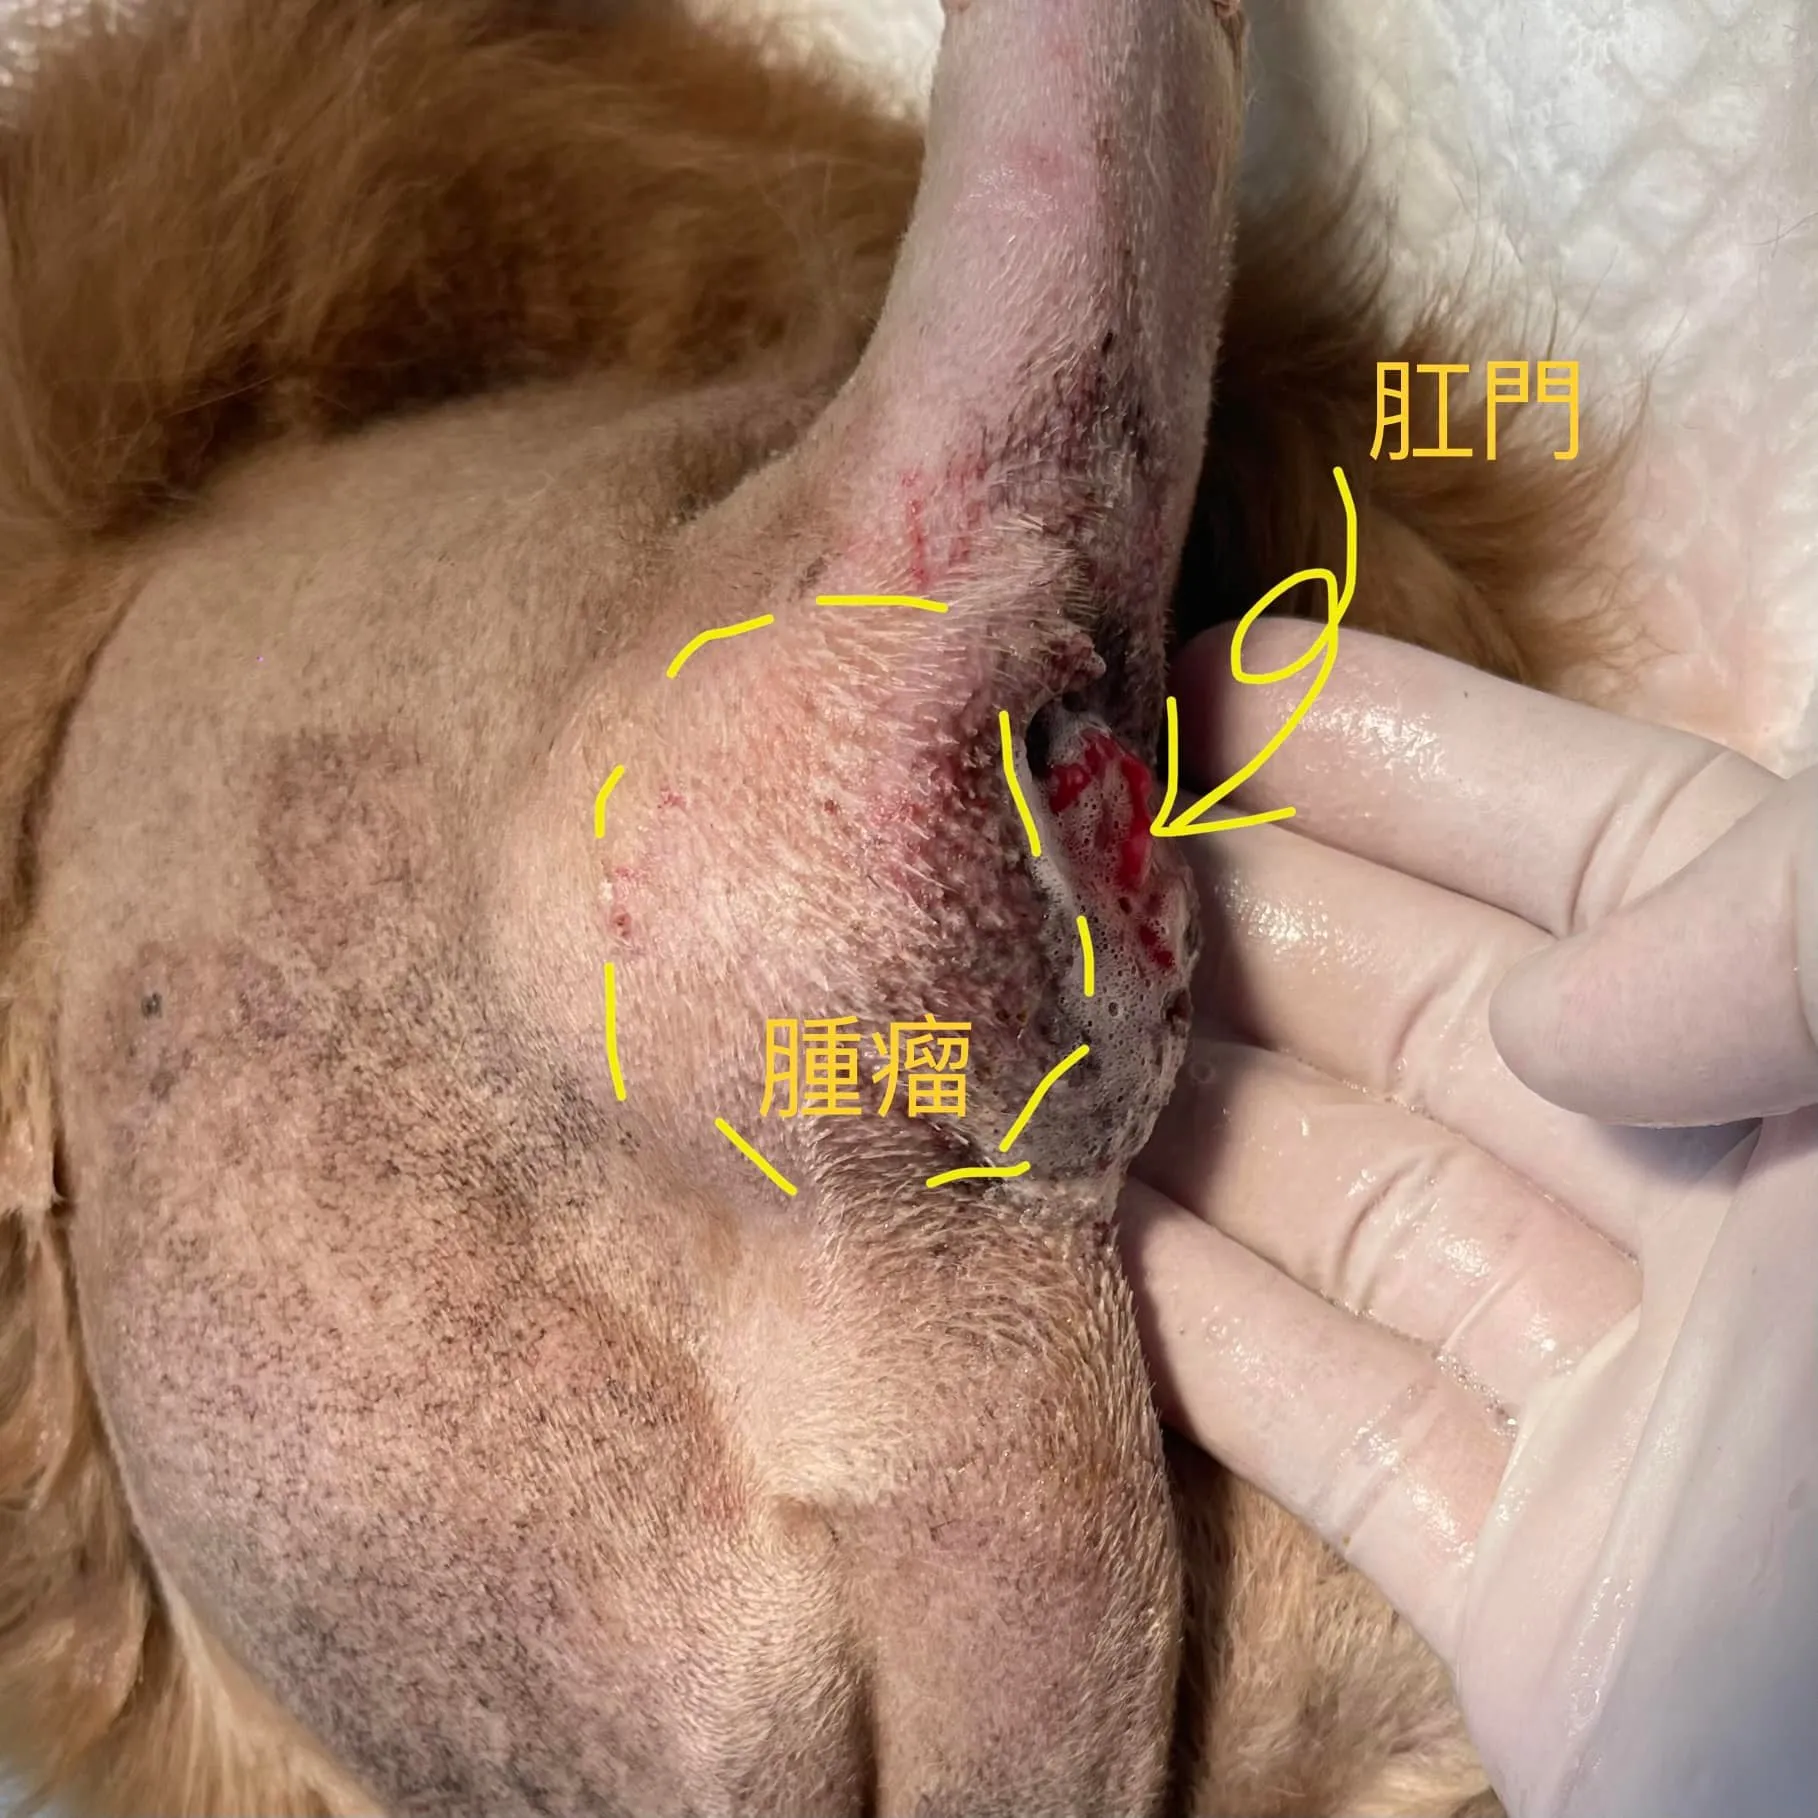

狗狗深藏不露的肛門囊癌

2026/02/06醫師在不同病患發現這個腫瘤的時候 ,幾乎是一個病患一個故事:「狗狗突然大便變得很細!」、「狗狗好像尿不出來,變得好虛弱!」、「他好像站不起來了,突然又吐又拉的!」「他健康檢查血鈣好高,但都找不到原因!